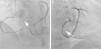

Caso clínicoApresentamos o caso de um homem de 65 anos de idade, observado em consulta de cardiologia por dor torácica atípica (tipo «moedeira», sem relação fixa com os esforços, durando poucos minutos) com quatro meses de evolução. Como fatores de risco cardiovascular apresentava tabagismo, dislipidemia e obesidade. O exame físico, o ECG e o ecocardiograma eram normais. Na prova de esforço verificou‐se ectopia ventricular muito frequente, com salvas de extrassístoles ventriculares consecutivas de morfologia variada, tanto no pico de esforço, como durante o início da recuperação. No entanto, não foram observadas alterações ST‐T significativas (Figura 1). O doente foi referenciado para realização de coronariografia que evidenciou artérias coronárias com irregularidades, mas sem estenoses significativas. A injeção seletiva na coronária esquerda revelou a visualização simultânea da porção distal da coronária direita, por enchimento retrógrado, através de uma conexão intercoronária entre a circunflexa (CX) e a coronária direita (CD) (Figura 2). A coronariografia direita evidenciou o preenchimento da circunflexa e da descendente anterior, através da mesma conexão (CD – CX), ao nível da crux (Figura 3). A variante da circulação coronária observada foi compatível com a descrição de continuidade coronária ou arcada coronária. Posteriormente, o doente realizou um Holter que evidenciou ritmo sinusal de base, com extrassistolia supraventricular ocasional, 120 extrassístoles ventriculares polimórficas isoladas e um par. Atualmente, o doente encontra‐se medicado com bloqueador‐beta e está assintomático.

Coronariografia direita (A – projeção OAE 20°, cranial 20°; B – projeção OAD 30°) evidenciando a conexão entre a coronária direita e a circunflexa (seta). A projeção no painel A relembra uma «arcada coronária» e a projeção no painel B permite a delineação do sulco auriculoventricular, com as aurículas para a esquerda e os ventrículos para a direita da imagem.